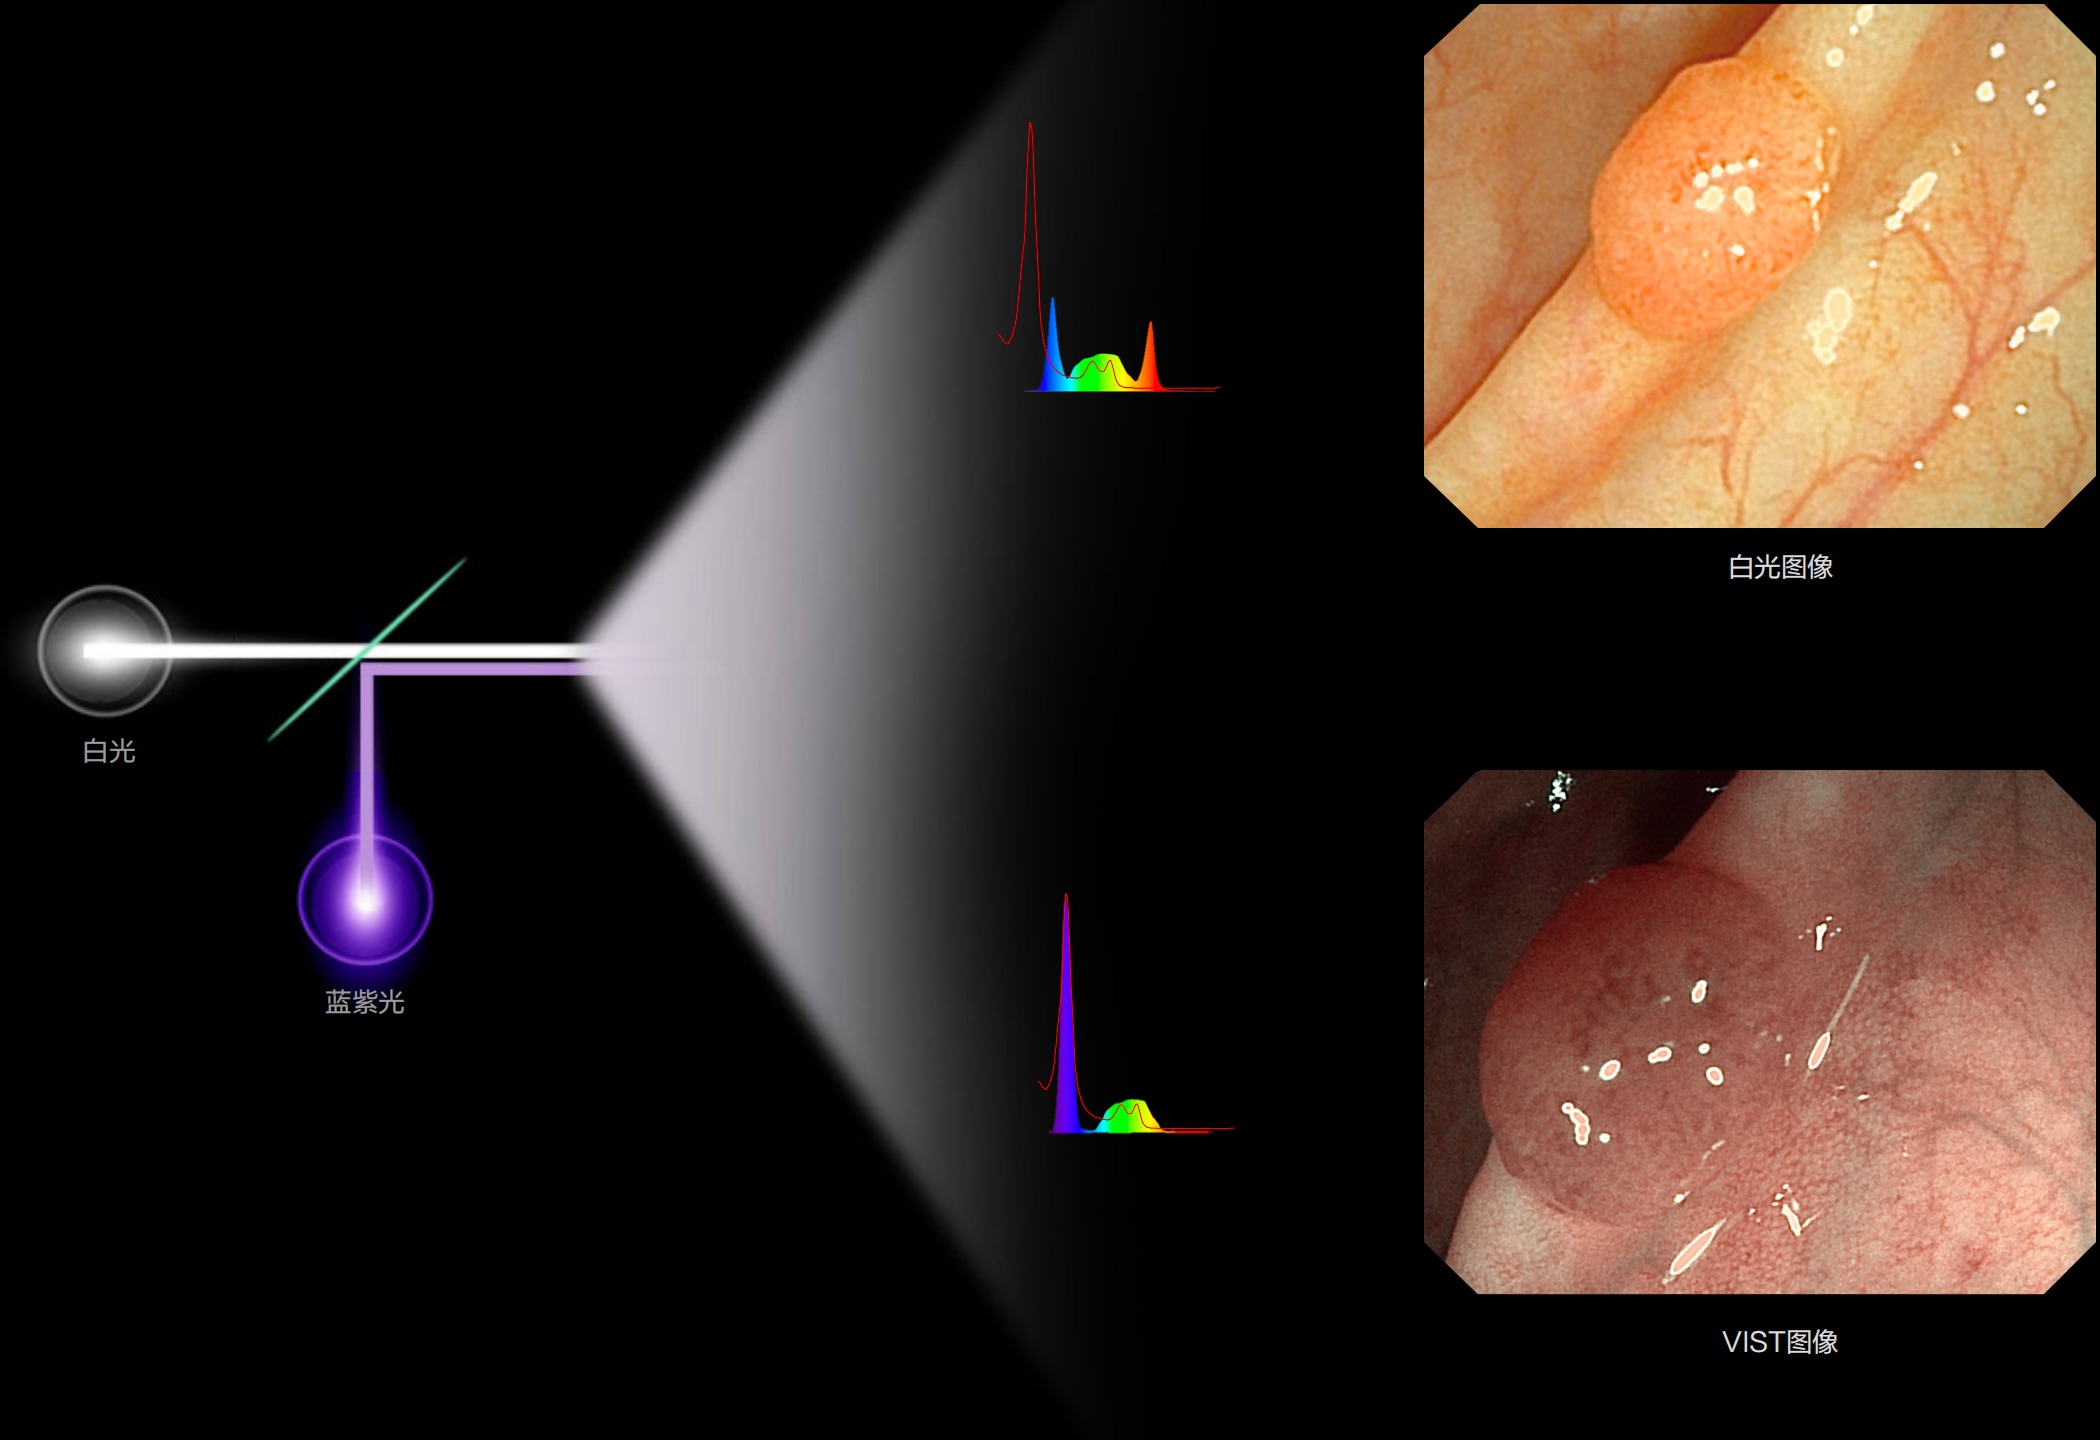

(Versatile Intelligent Staining Technology)

能够凸显黏膜浅层血管轮廓和黏膜表面微结构,适用于中、近景观察下的早癌精确诊断。

白光图像

SFI图像